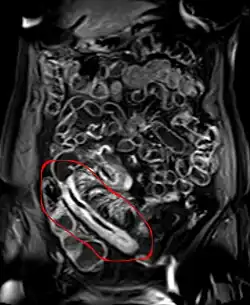

Pathologisches Präparat eines operativ entfernten Darmstücks